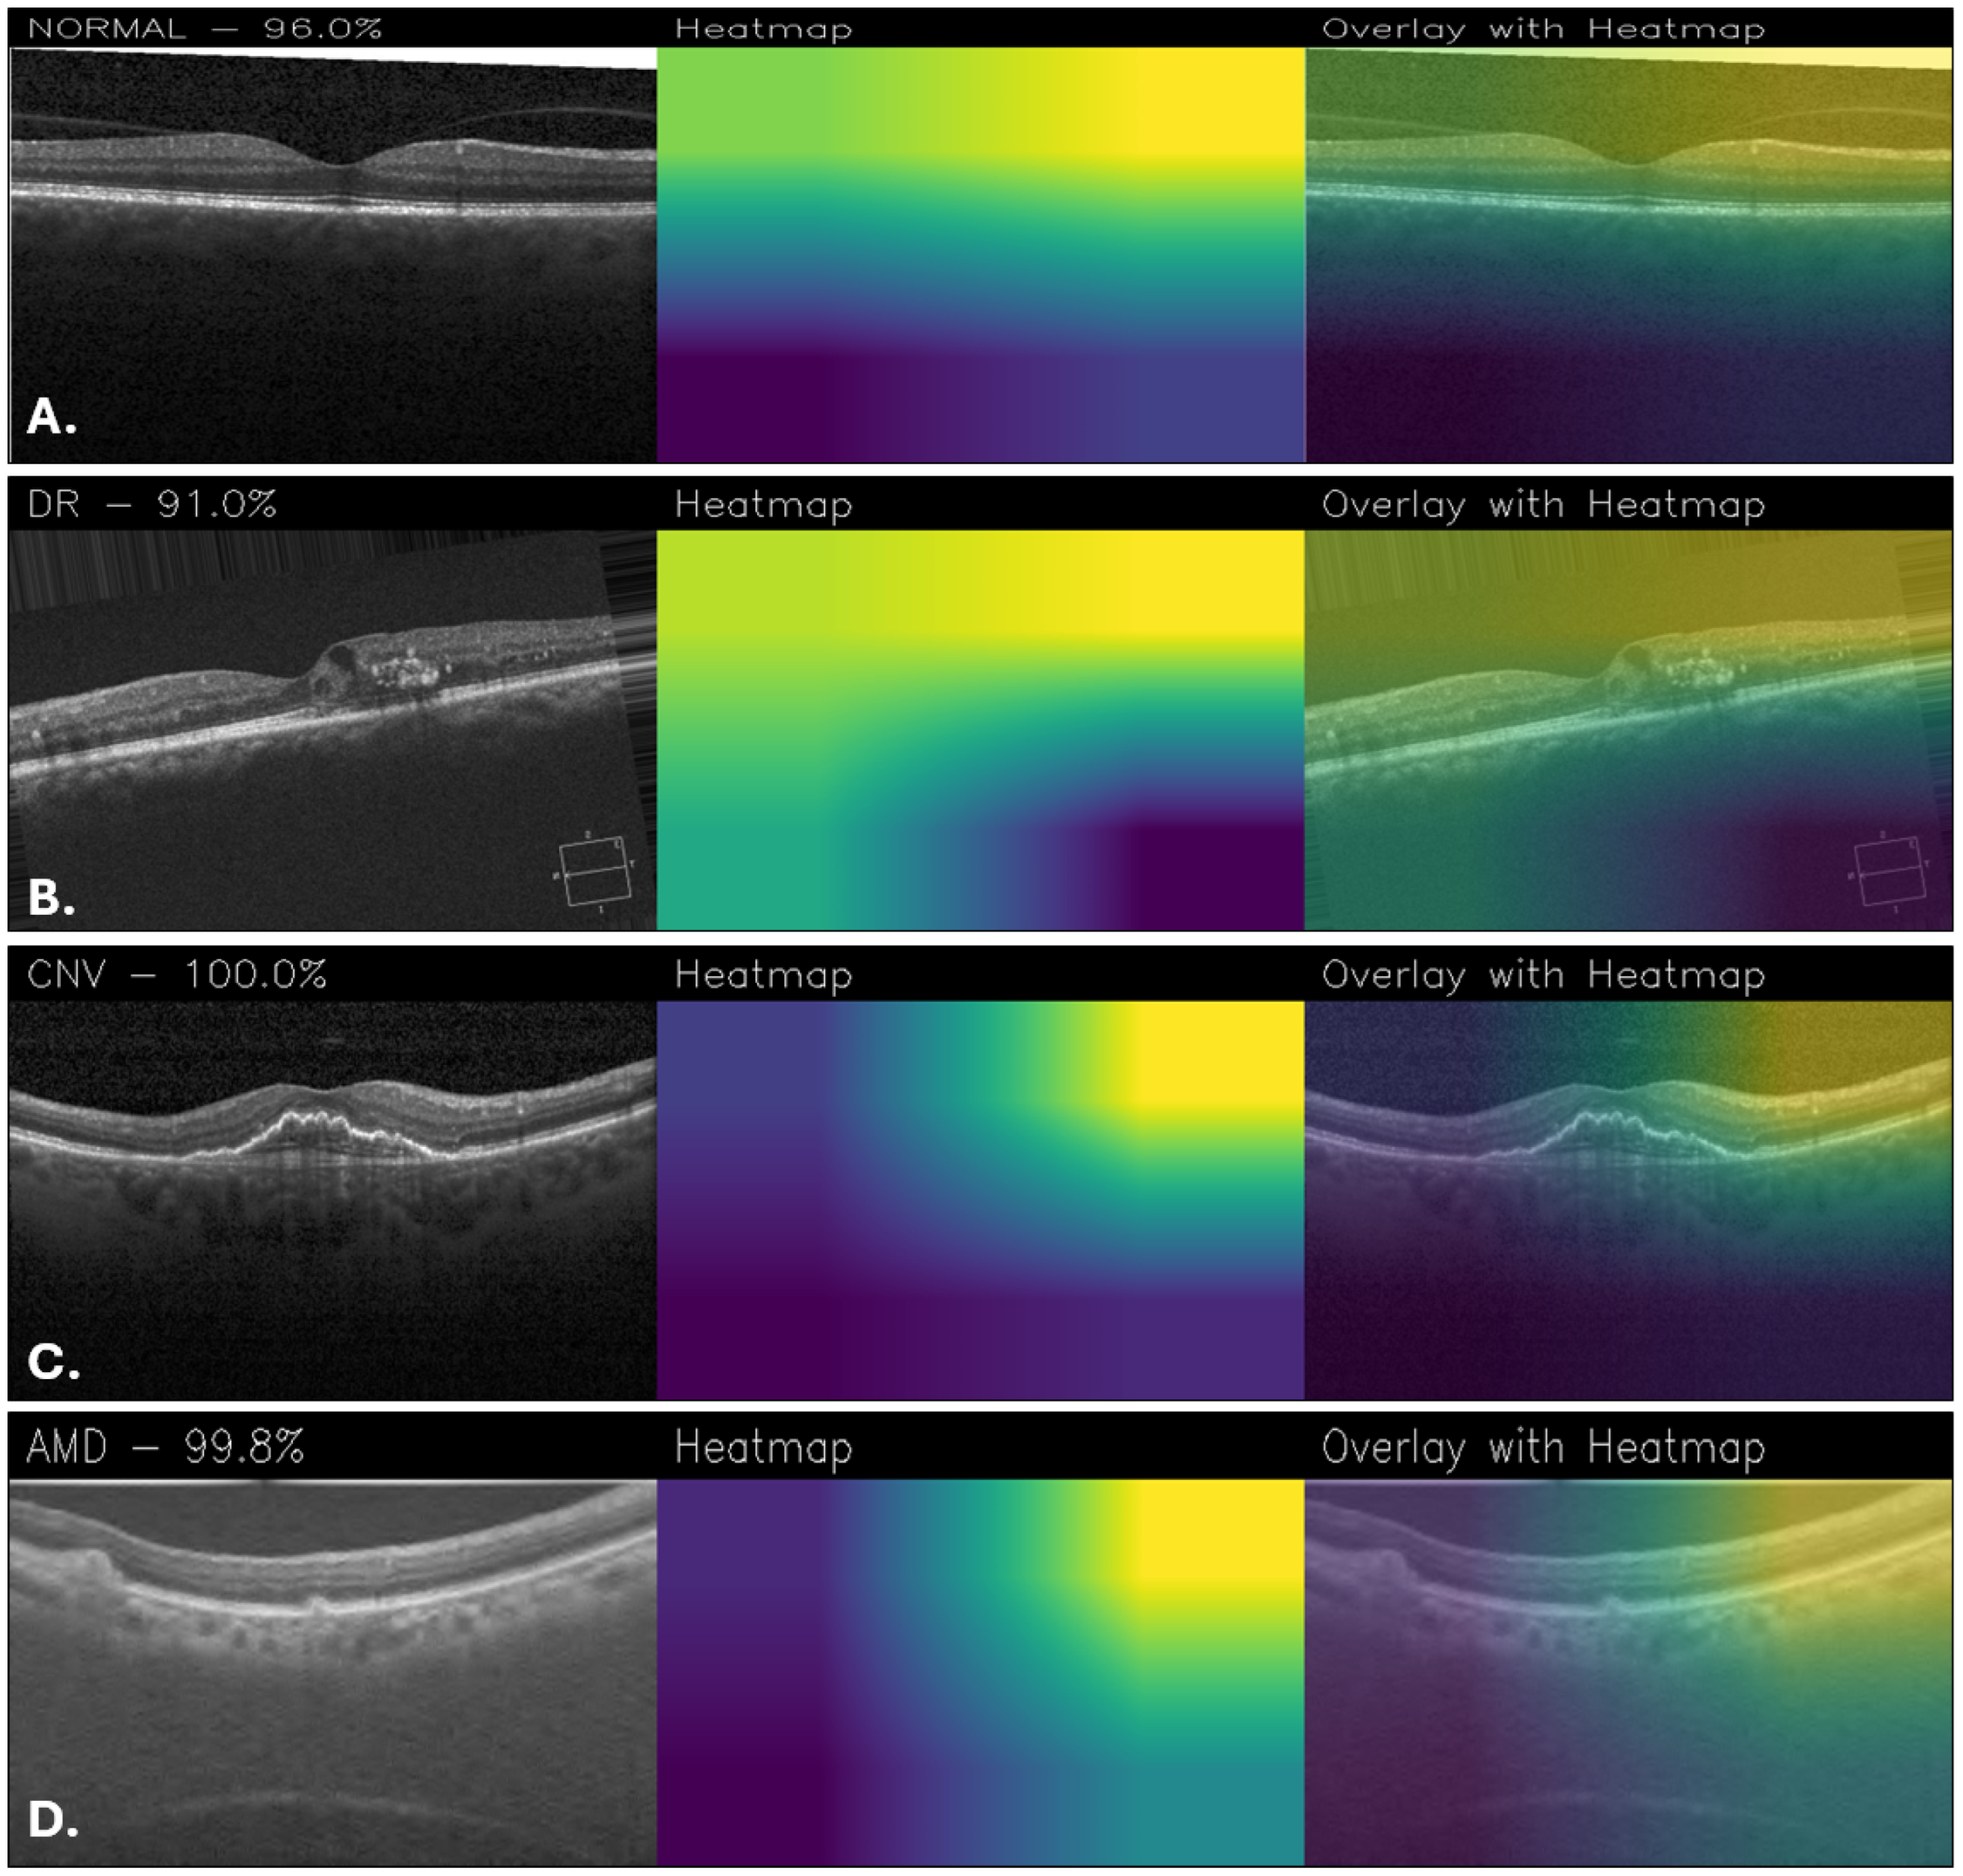

The explainability is critical to understand which areas of the images are used for classification, so activation maps were generated with Grad-CAM. According to them, NeoNet focuses attention on specific and relevant regions of retinal images, suggesting a good ability to learn discriminative patterns. However, for example, the Grad-CAM maps of CUSTOM_CNN are more accurate and detailed, showing better localization of salient features than NeoNet. This aspect suggests that despite the higher overall accuracy of NeoNet, CUSTOM_CNN may offer greater transparency in decision making, a crucial factor in medical fields. Figure 10 shows a series of classification examples made through the use of the NeoNet model. For each of the four retinal conditions (NORMAL, DR, CNV, and AMD), the following cases are shown: the original image (left), the heatmap of model activations (middle), and the overlay of the heatmap on the image (right). The highlighted regions indicate the areas that most influenced the classification.

In the Grad-CAM overlays, the normal case (Figure 10A) shows concentrated activation at the foveal pit and adjacent retinal layers. For DR (Figure 10B), attention is directed toward the superior retinal boundary and areas with localized structural abnormalities. In CNV (Figure 10C), the model emphasizes the central lesion and surrounding retinal thickening. For AMD (Figure 10D), activation is distributed along the retinal pigment epithelium and subretinal regions, highlighting drusen-like changes.

Figure 10. Grad-CAM visualizations obtained with NeoNet for healthy retina (A), DR (B), CNV (C), and AMD (D).